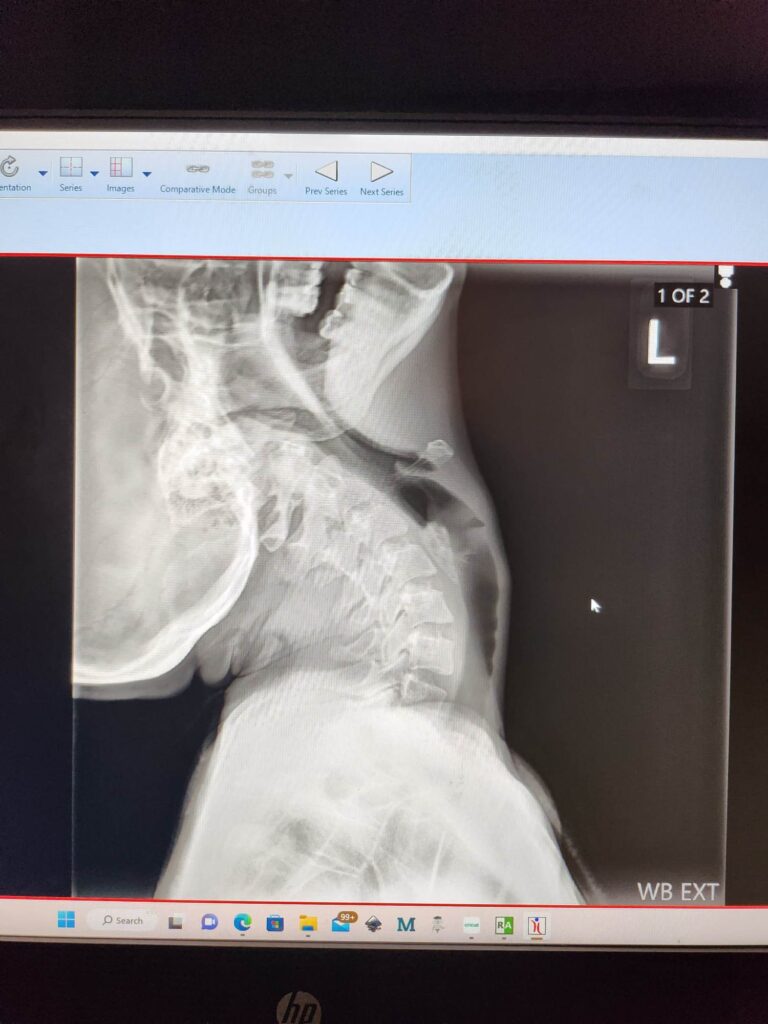

Joint laxity and instability are common nuisances for us. Since the connective tissue that holds everything together is weakened, our necks struggle to keep our head upright, often leaving our heads feeling like a bowling ball that’s too heavy for our bodies, or most often described as a bobble head. This commonly leads to cranial cervical instability (CCI) and/or Atlanto-axial instability (AAI). Basically, that means thereâs abnormal movement between the skull and the top part of the spine, which should be stable but isnât.

Our body works overtime and our muscles overcompensate just to keep the head up, and because of that, the neck and shoulder muscles are constantly tight, sore, and worn out, leaving the head feeling unsteady. When you think about how important the spine is for everything, it makes sense that this kind of instability can cause a lot of neurological symptomsânerve compression, dizziness, head pressure, nausea and so much more. Sadly, this is really common in people with EDS, but because of how subtle or complex it can be, itâs often missed or misdiagnosed without the right testing.

- And other comorbidities such as Chiari Malformation, Cranial Cervical Instability (CCI) or Atlanto-Axial Instability (AAI), Tethered Cord Syndrome, Cerebrospinal Fluid (CSF) Leaks, Intracranial Hypertension (IIH), Dysautonomia such as Postural Orthostatic Tachycardia Syndrome (POTS), and more